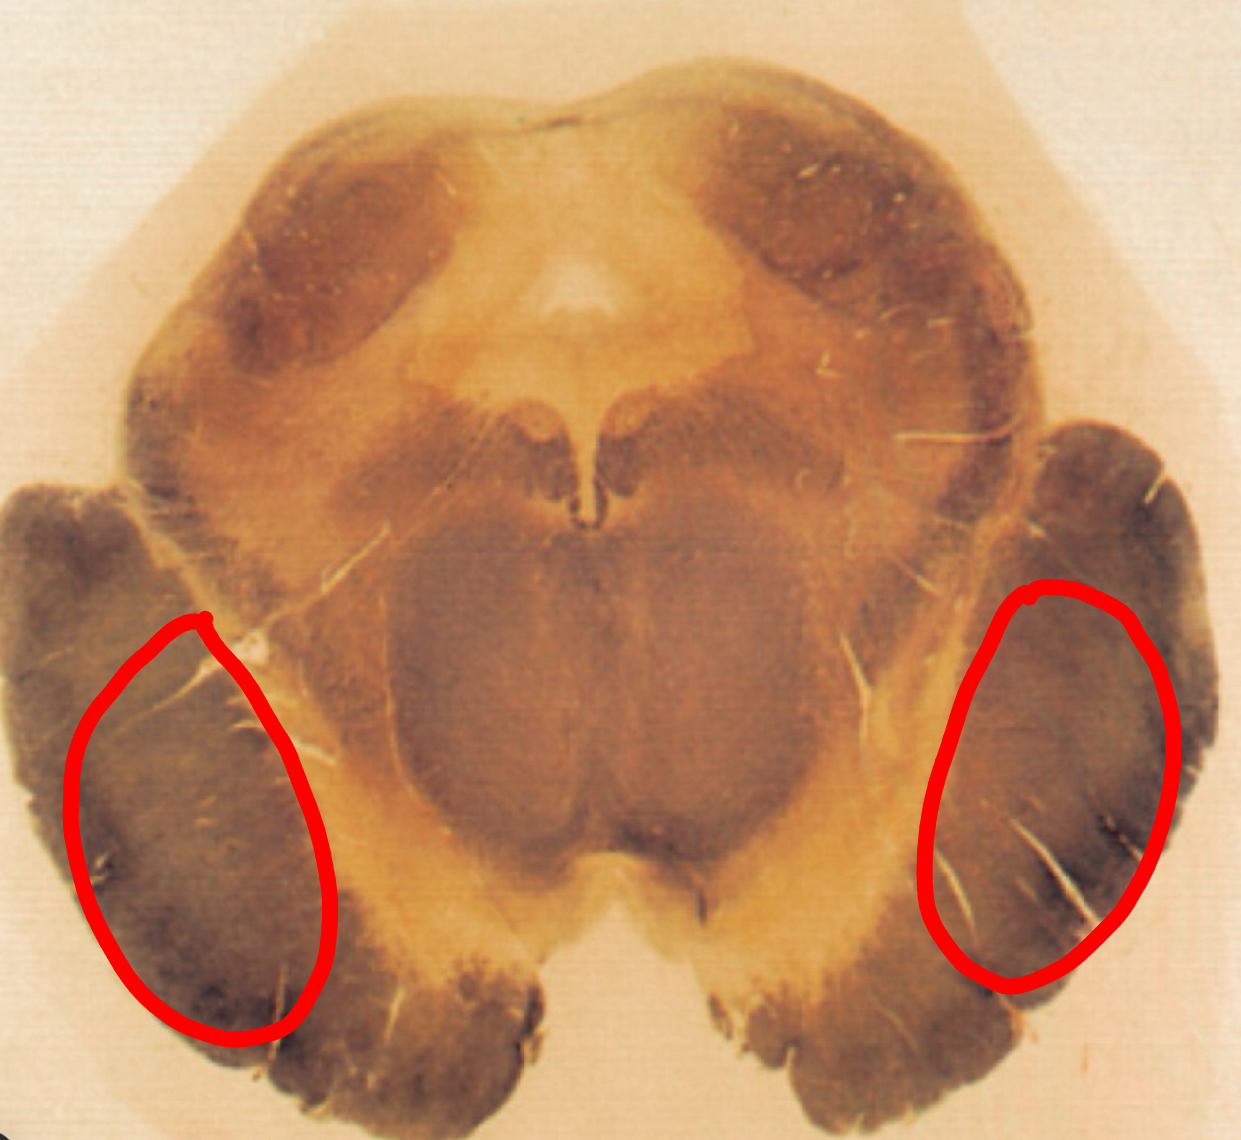

fastigial nucleus

interposed nucleus (globose + emboliform)

dentate nucleus

posterior lobe

vermis

tonsils

flocculus

nodule

cerebellar peduncles

4th ventricle